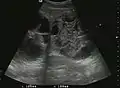

Liver cysts

They can be single or multiple, with variable size, generally less than 20 mm (congenital). Rarely, sizes can reach several centimeters, leading up to the substitution of a whole liver lobe (acquired, parasitic). They may be associated with renal cysts; in this case the disease has a hereditary, autosomal dominant transmission (von Hippel Lindau disease).

The ultrasound appearance is a well defined lesion, with very thin, almost unapparent walls, without circulatory signal at Doppler or CEUS investigation. The content is transonic suggesting fluid composition. The presence of membranes, abundant sediment or cysts inside is suggestive for parasitic, hydatid nature. Posterior from the lesion the acoustic enhancement phenomenon is seen, which strengthens the suspicion of fluid mass. They typically displace normal liver vessels but no vascular or biliary invasion occurs.

Liver cyst

Hydatid liver cyst. Diagnostic criteria are the presence of membranes and sediment inside.